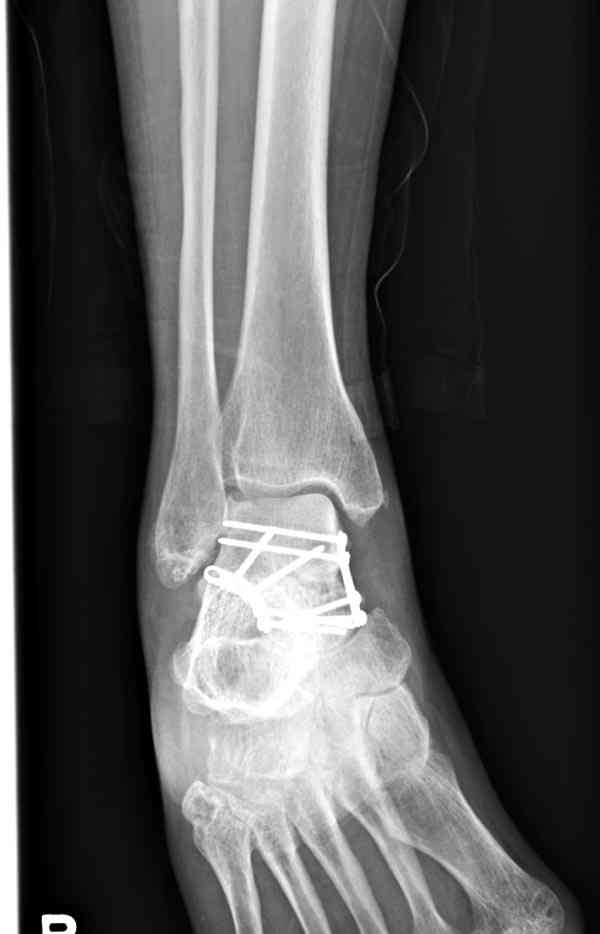

И второй случай из недавней ташкентской практики, (извините за качество ренгенограммы и только в одной проекции) случай падения с высоты (кстати моего друга - известного киноактера) - открытый

смещенный перелом тарана, с переломом переднего края дистального эпиметафиза большеберцовой кости.

При поступлении в приемной сделана первичная обработка с ушиванием открытой латеральной раны и вытяжением за пятку.

Из-за отсутствия времени пришлось оперировать на второе утро, из материала, что имеем на месте, фиксирован двумя шурупами, а третий-это контур сломанного жойстика в 4 мм. На дистальный медиальный конец тибиа antiglide 3.5 мм пластина. Через пару дней выписан и несмотря на предупреждение, самостоятельно начал нагрузку в 4 недели, время не ждет, снимается в боевике в Росийской Федерации.